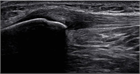

1. ジャンパー膝はジャンプやランニング動作を繰り返すスポーツ選手に好発する膝蓋腱近位部のスポーツ障害である。

1. ジャンパー膝の場合、超音波画像検査を行う事が推奨される(推奨度1)